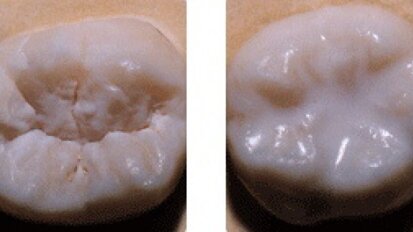

L'hypoplasie de l'émail (HE) est une anomalie de l'émail dentaire qui résulte en une quantité d'émail moindre que la ...